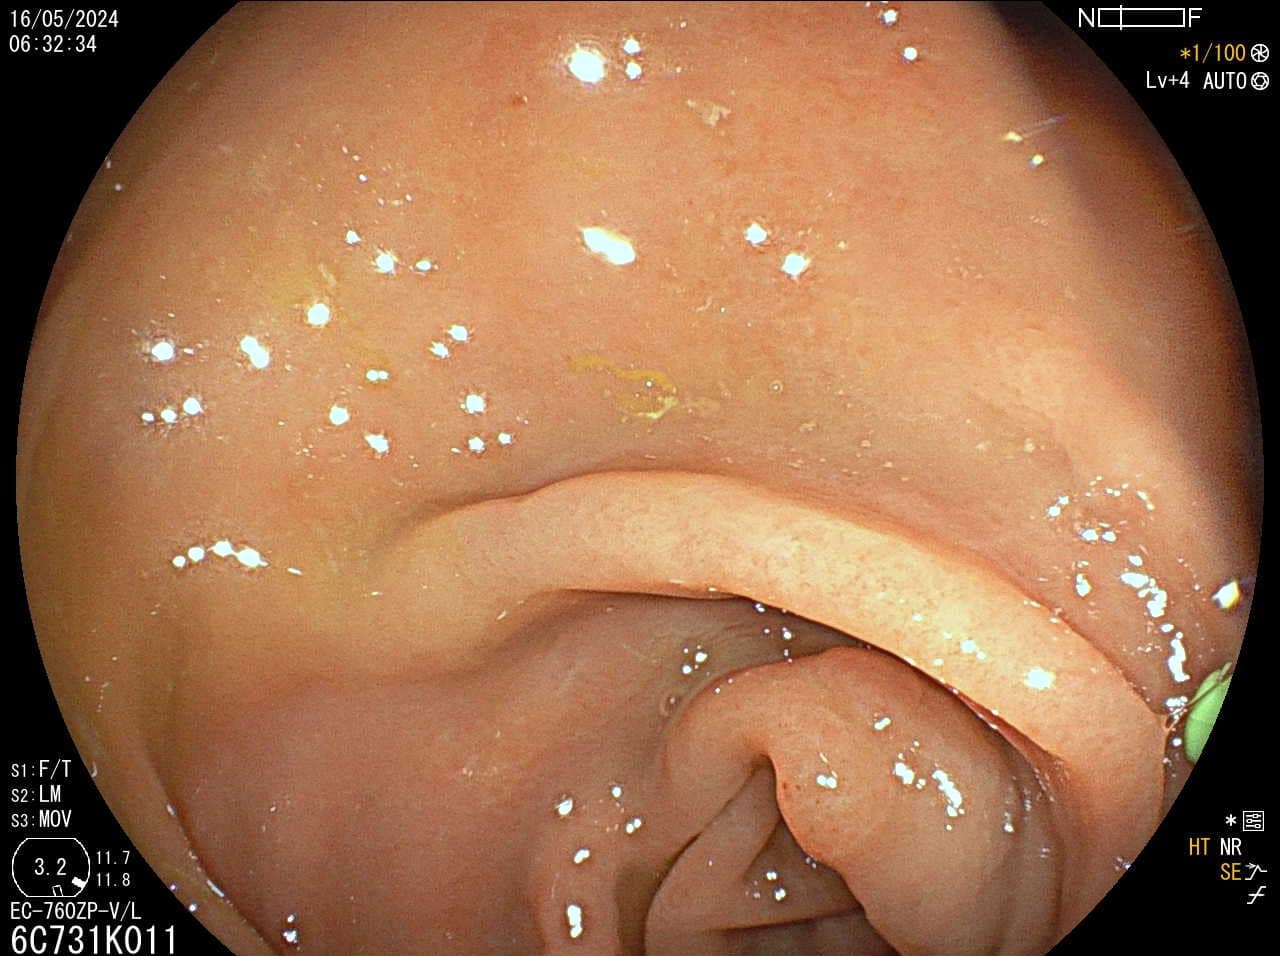

Pregled debelog crijeva

Kako bi pregled debelog crijeva bio temeljit potrebna je dobra priprema crijeva (očišćenost), no mali i plitki polipi, unatoč optimalnim uvjetima pretrage mogu ostati nezamijećeni, a zbog anatomije crijeva i skriveni iza nabora.